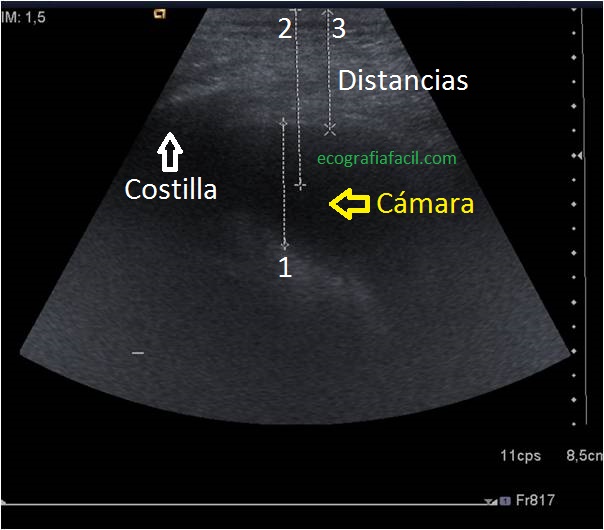

En esta primera imagen vemos una cámara líquida correspondiente a un derrame pleural y las medidas estándar que realizamos como información previa a la Toracocentesis.

In this first image we see a liquid chamber corresponding to a pleural effusion and the standard measurements that we made as prior information to the Toracocentesis.

Si van a pinchar el derrame, marcaremos con una cruz la zona de punción, donde la cámara de líquido es mayor y mediremos dicha cámara y la distancia de la piel al derrame.

THE PATIENT: Normally the patient must be seated with his back to us, we can raise the arm of the affected side and support it in the head relaxed.We must look for the intercostal space, the ribs will be our worst enemies, through the spaces Let us see the pathology.If they are going to puncture the effusion, we will mark with a cross the puncture area, where the liquid chamber is larger and we will measure said chamber and the distance of the skin to the effusion.